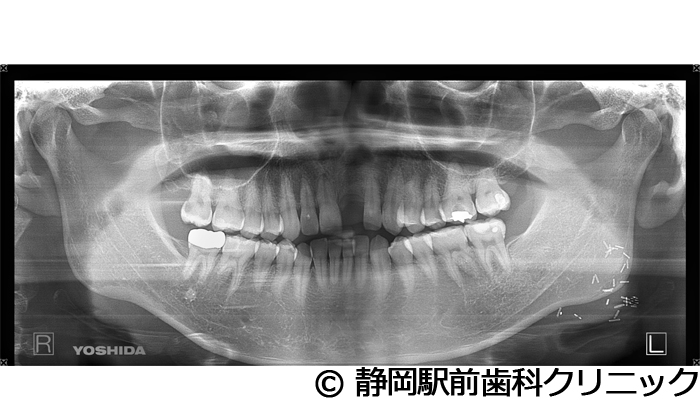

【症例3】右下インプラント埋入

- 治療前

- 治療後

- 治療名

- 右下インプラント埋入

- 費用

- 440,000円(税込)

- 期間

- 6ヵ月

治療内容

患者様の症状

右下の歯が折れてしまい、食べにくいため、インプラント治療希望。

治療方法

右下2本は抜歯を行い、骨の治癒後にCTを撮影し、詳細に治療計画を立案しました。その後、インプラントを埋入し、人工歯を被せて咬合の回復を行いました。

治療結果

患者様からは右でも好きな物を食べることができるようになり、喜んでいただきました。人工歯はセラミックにて作成し、見た目もご満足いただけました。

※治療結果は個人差があります。

治療を行う上での注意点(リスク・副作用)

術後は、出血、腫れ、痛みなどが出る可能性があります。